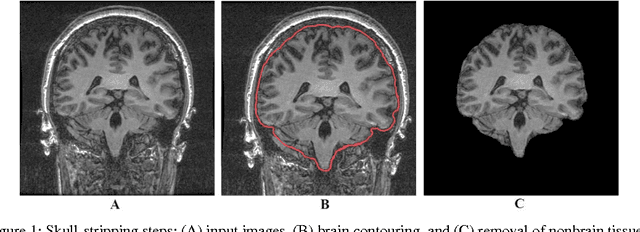

Abstract:The hippocampus is a seminal structure in the most common surgically-treated form of epilepsy. Accurate segmentation of the hippocampus aids in establishing asymmetry regarding size and signal characteristics in order to disclose the likely site of epileptogenicity. With sufficient refinement, it may ultimately aid in the avoidance of invasive monitoring with its expense and risk for the patient. To this end, a reliable and consistent method for segmentation of the hippocampus from magnetic resonance imaging (MRI) is needed. In this work, we present a systematic and statistical analysis approach for evaluation of automated segmentation methods in order to establish one that reliably approximates the results achieved by manual tracing of the hippocampus.